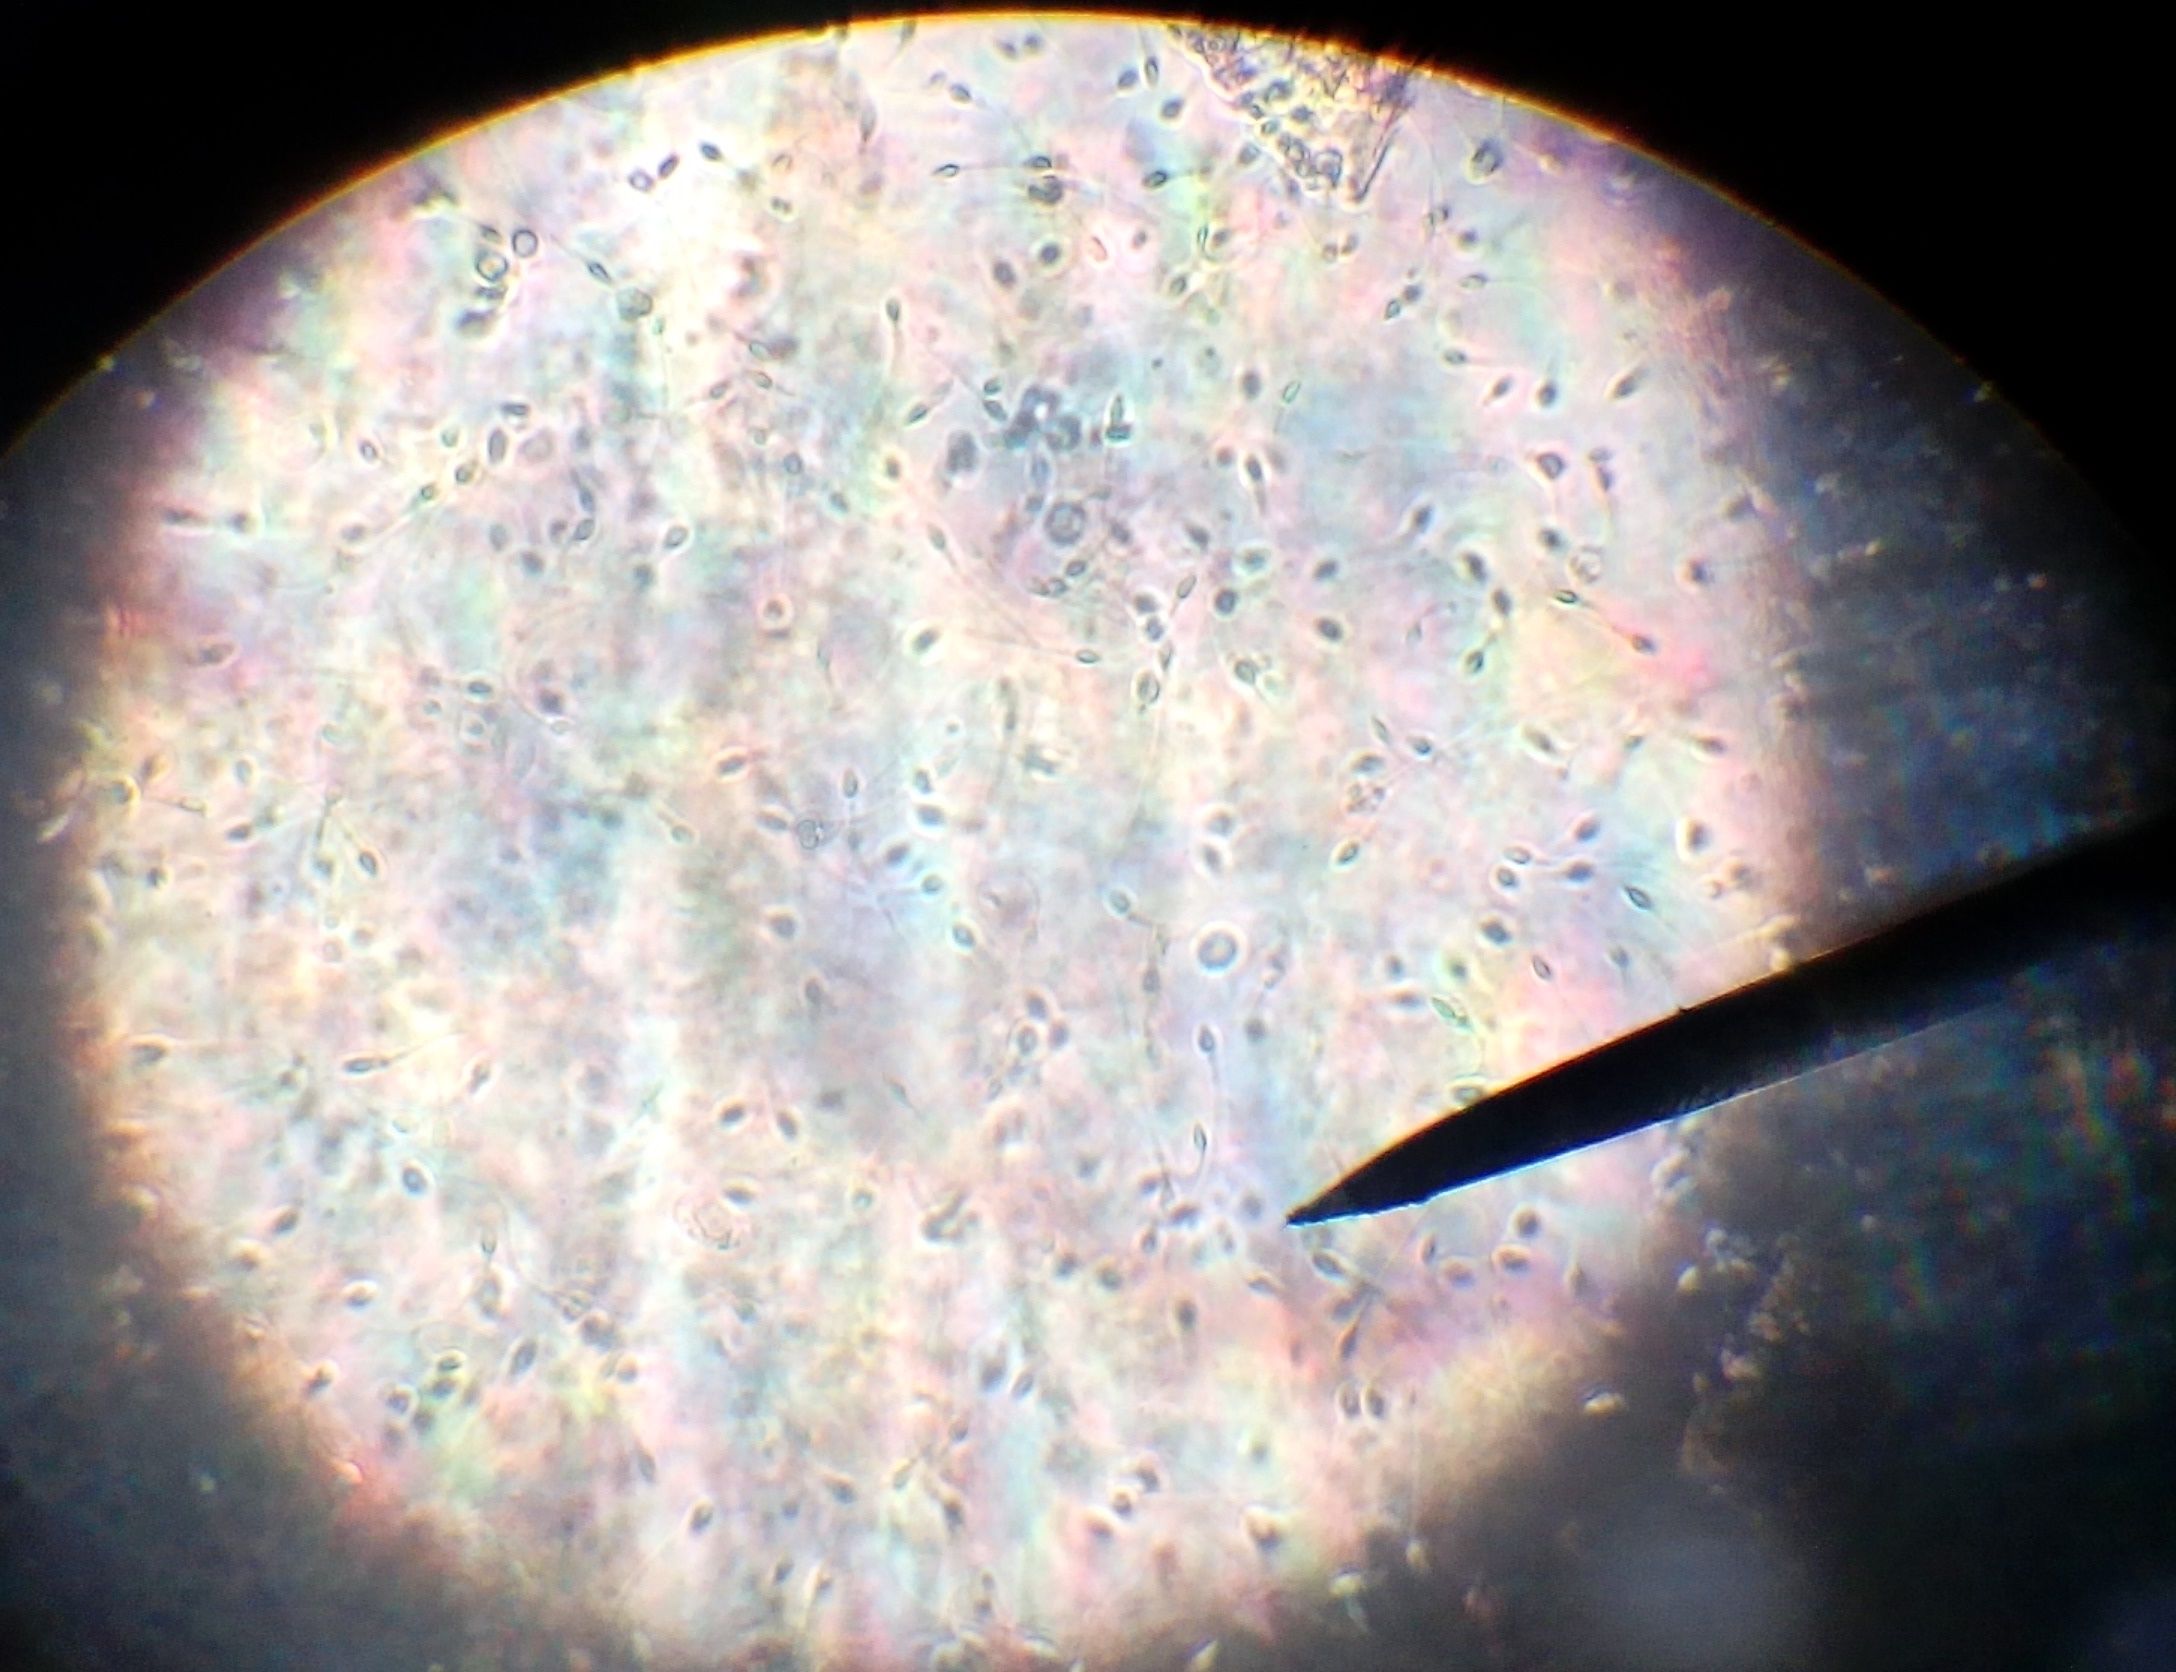

2. muestra de sangre en microscopio

1. se observo globulo rojo

2. muestra de espermatozoides se observaron en movimiento, estas celulas reproductoras del hombre, depues de cierto tiempo los espermas mueren por no estar en un ambien apto